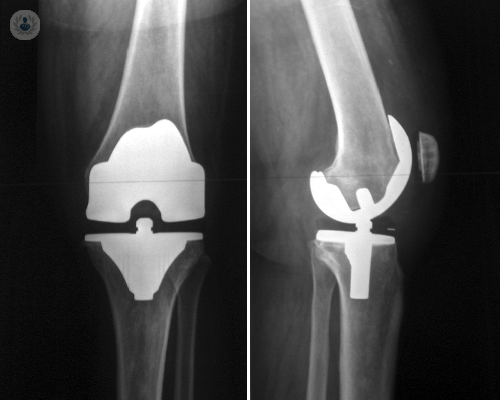

• Cirugía de Prótesis de Rodilla

Artículos médicos de Cirugía de Prótesis de Rodilla

Cirugía guiada en prótesis de rodilla

La cirugía guiada en colocación de prótesis es una técnica muy precisa que reduce los riesgos y tiene resultados muy óptimos. Descubre otras ventajas de la cirugía guiada gracias al Dr. Revenga Giertych, especialista en Traumatología.